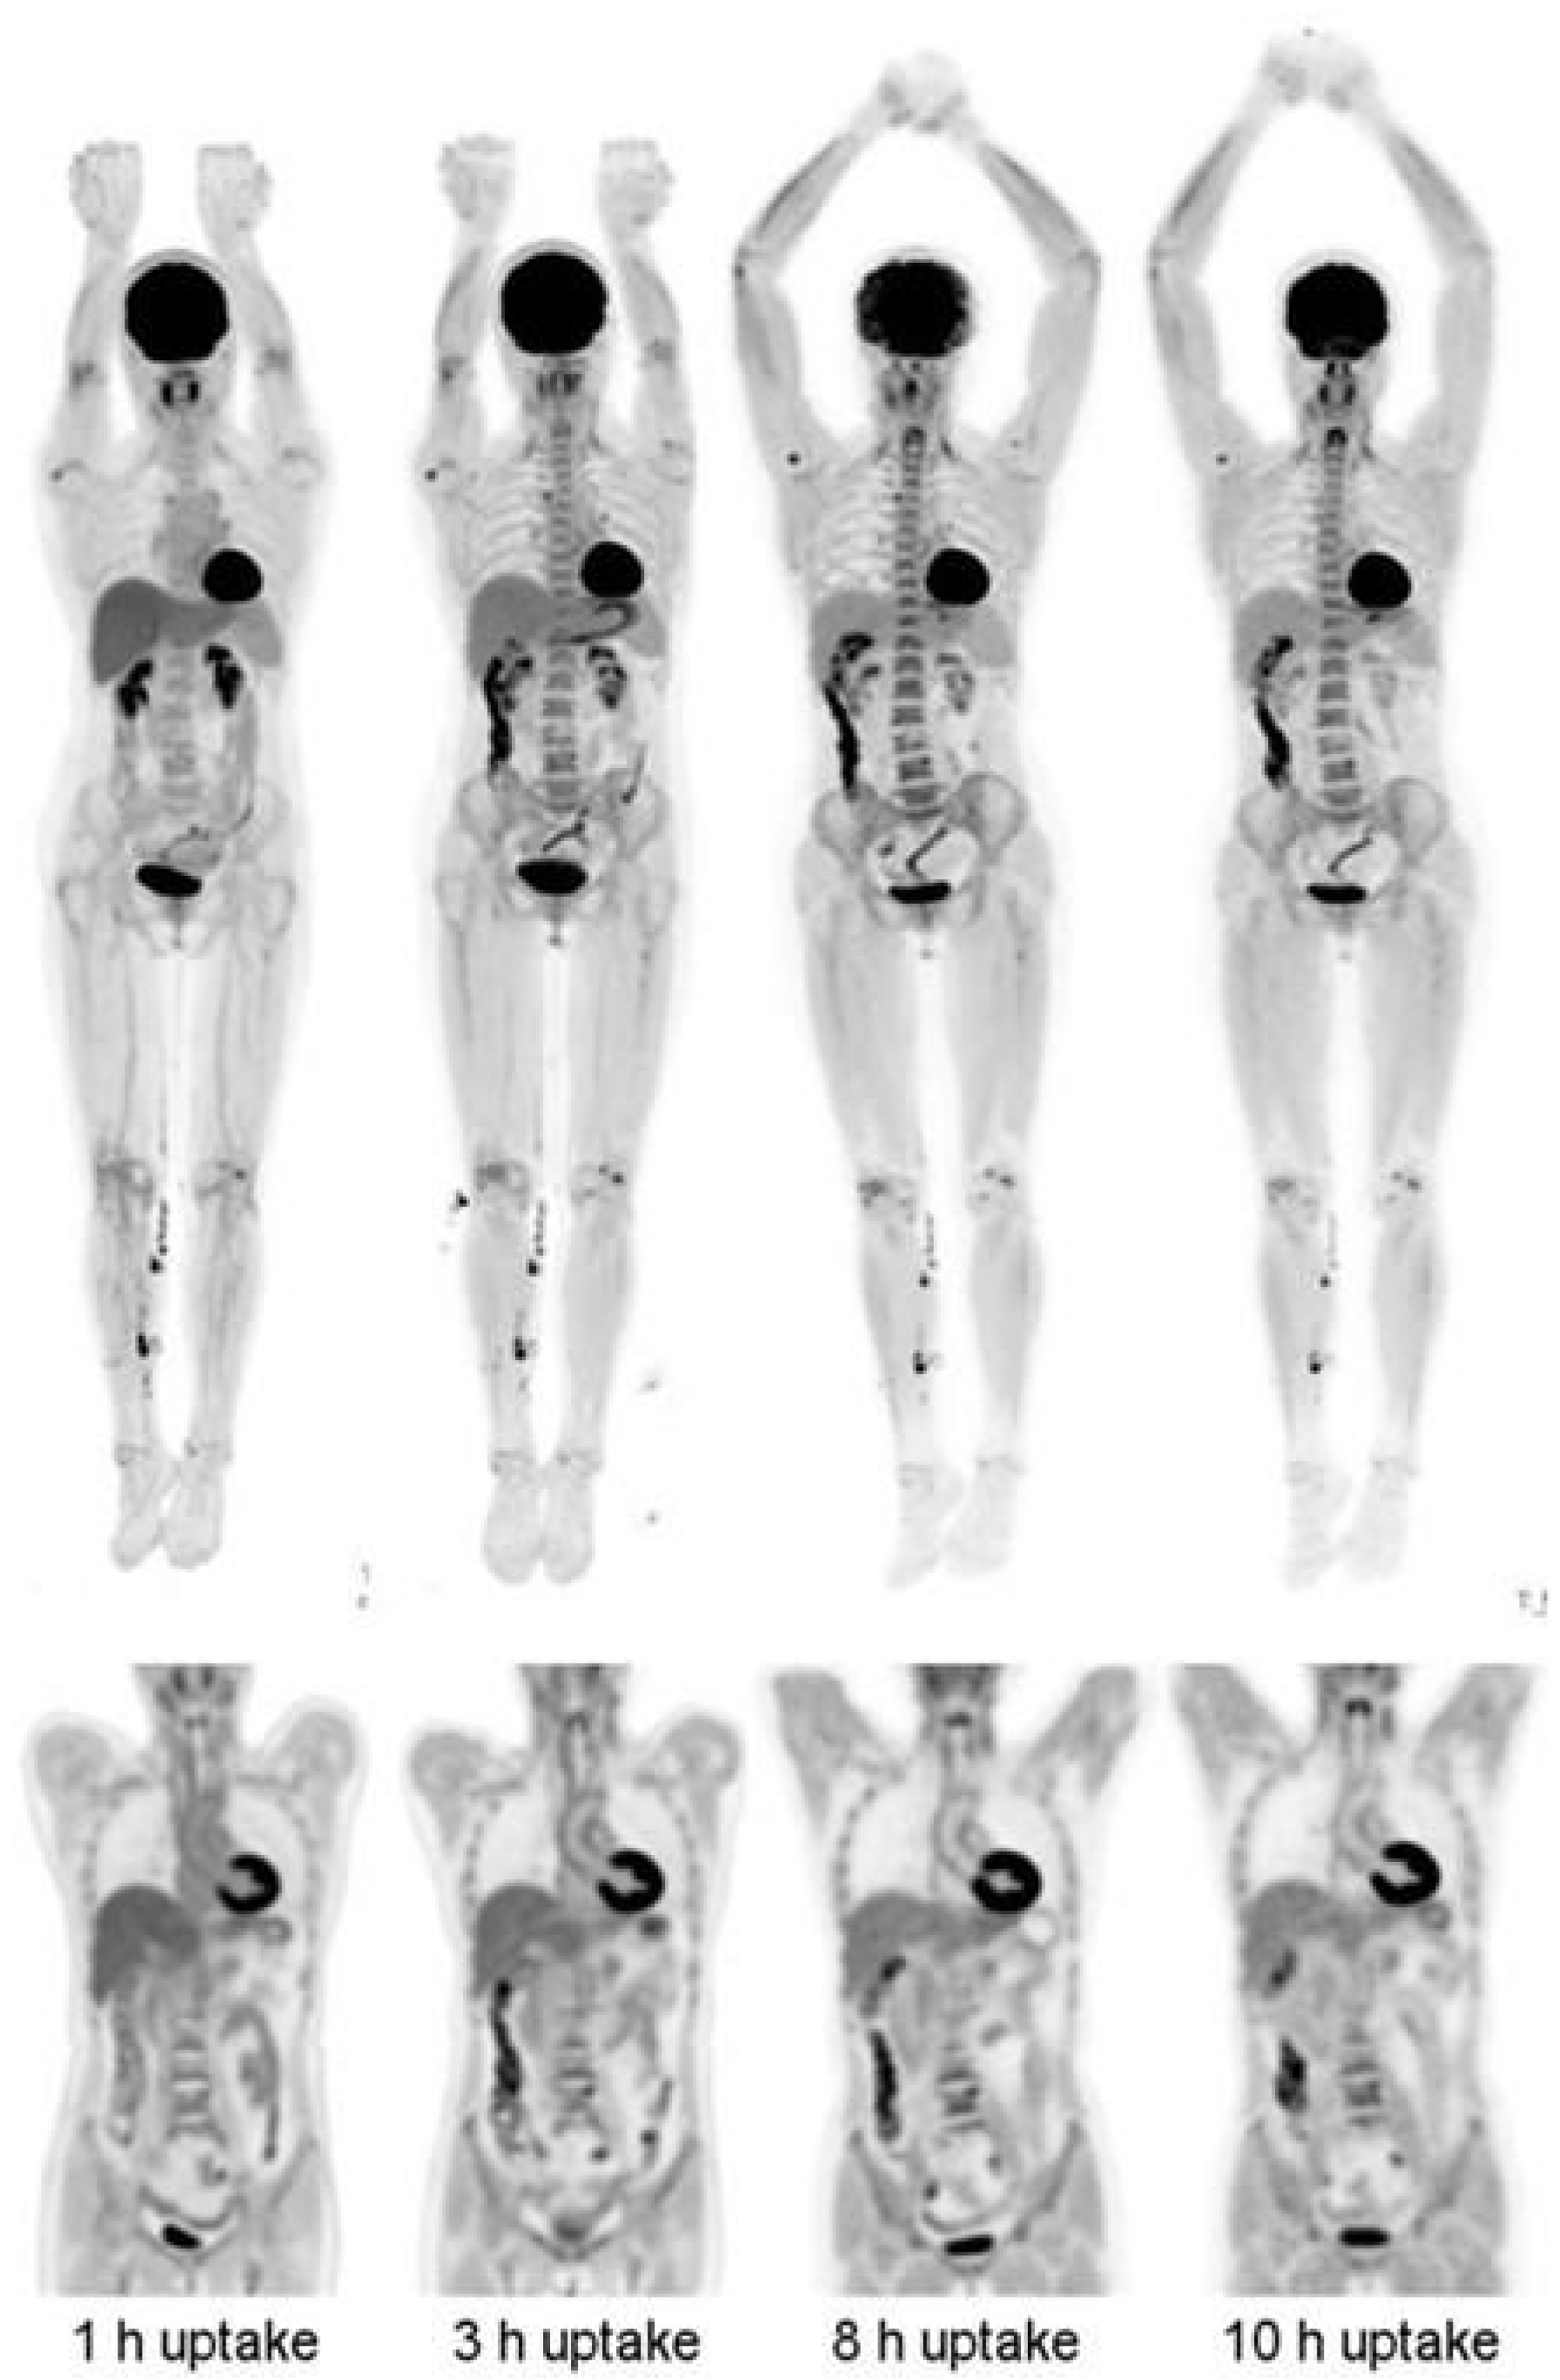

4. Longitudinal and Delayed Imaging

- Basu, S.; Kung, J.; Houseni, M.; Zhuang, H.; Tidmarsh, G.F.; Alavi, A. Temporal profile of fluorodeoxyglucose uptake in malignant lesions and normal organs over extended time periods in patients with lung carcinoma: Implications for its utilization in assessing malignant lesions. Q. J. Nucl. Med. Mol. Imaging 2009, 53, 9–19. [Google Scholar]

- Cheng, G.; Alavi, A.; Lim, E.; Werner, T.J.; Del Bello, C.V.; Akers, S.R. Dynamic changes of FDG uptake and clearance in normal tissues. Mol. Imaging Biol. 2013, 15, 345–352. [Google Scholar] [CrossRef]

- Badawi, R.D.; Shi, H.; Hu, P.; Chen, S.; Xu, T.; Price, P.M.; Ding, Y.; Spencer, B.A.; Nardo, L.; Liu, W.; et al. First Human Imaging Studies with the EXPLORER Total-Body PET Scanner. J. Nucl. Med. 2019, 60, 299–303. [Google Scholar] [CrossRef]